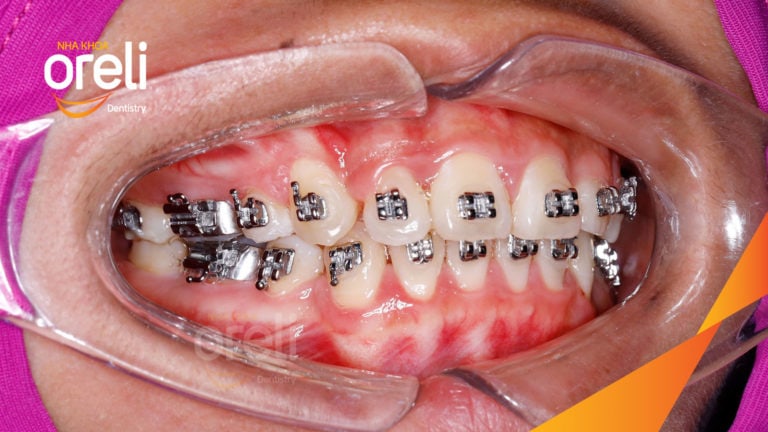

Ca niềng chỉnh chen chúc sai khớp cắn hạng 3 móm nhẹ – Kết quả thực tế ở Oreli Niềng răngChen chúcMóm Xem thêm